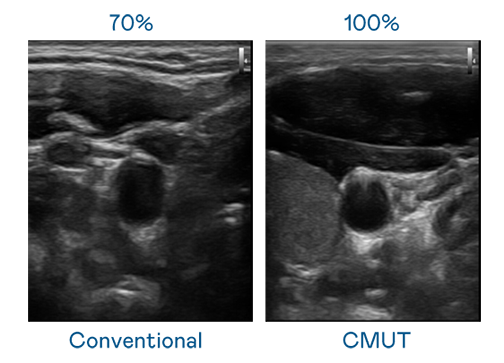

CMUT 技术是一种用电容式微机电元件来产生超音波讯号的技术。与传统 PZT 压电式技术相比,CMUT 频宽增加 30%,更宽频的超音波讯号让影像解析度大幅提升,是实现高影像品质医疗超音波扫描、促进精准医疗发展的关键技术。

超音波影像的解析度高低,首先取决于探头能发出的讯号频宽。龙门国际 CMUT 可提供高清晰的超音波讯号,提供高频宽、高灵敏度、影像纹理细节更高的超音波影像,协助医护人员缩短影像判读时间及利用精准的医疗影像进行诊断。